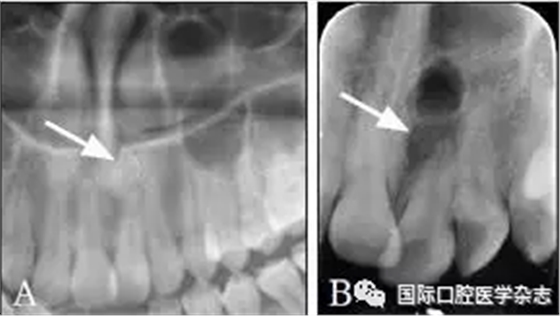

典型病例5 患者上前牙區(qū)疼痛2月,初診為11牙牙髓炎,開髓引流后癥狀未完全緩解。臨床檢查:11牙已開髓,21牙牙髓電測試有反應(yīng)。X線片示11、21牙根尖區(qū)有橢圓形囊腫影像,有致密骨白線。CBCT示低密度病損與鼻腭管相通,形態(tài)規(guī)則,界清??紤]鼻腭管囊腫,轉(zhuǎn)診至外科行上頜骨囊腫刮治術(shù),術(shù)后病理證實為鼻腭管囊腫。術(shù)后1年復(fù)查,病變區(qū)骨質(zhì)密度恢復(fù)(圖5)。

A:術(shù)前X線片;B~D:術(shù)前CBCT圖像;E、F:蘇木精-伊紅染色切片,證實為鼻腭管囊腫;G:術(shù)后1年復(fù)查X線片,病變區(qū)骨質(zhì)密度恢復(fù)。

圖 5 鼻腭管囊腫

Fig 5 Nasopalatine duct cyst